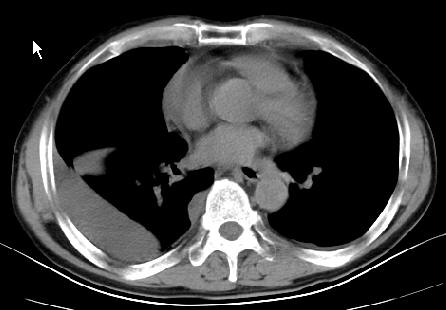

以下是引用草之原在2009-5-2 19:29:00的发言:[br]1.考虑右侧中心型肺ca纵膈淋巴结转移,双侧胸腔积液及右侧叶间裂积液,心包积液。[br]2.两肺上叶病灶,纵膈窗显示部分病灶硬化,考虑:结核。[br][br] [br]

以下是引用ct诊断高手在2009-5-2 19:08:00的发言:[br]我考虑右侧中央型肺癌 伴右肺节段性不张,两肺及纵隔淋巴结转移,右侧胸腔积液。

以下是引用zjzjr在2009-5-2 20:16:00的发言:[br]肺结核,转移瘤.纵隔淋巴结转移或淋巴瘤,右侧包裹性积液、斜裂积液。心包积液。